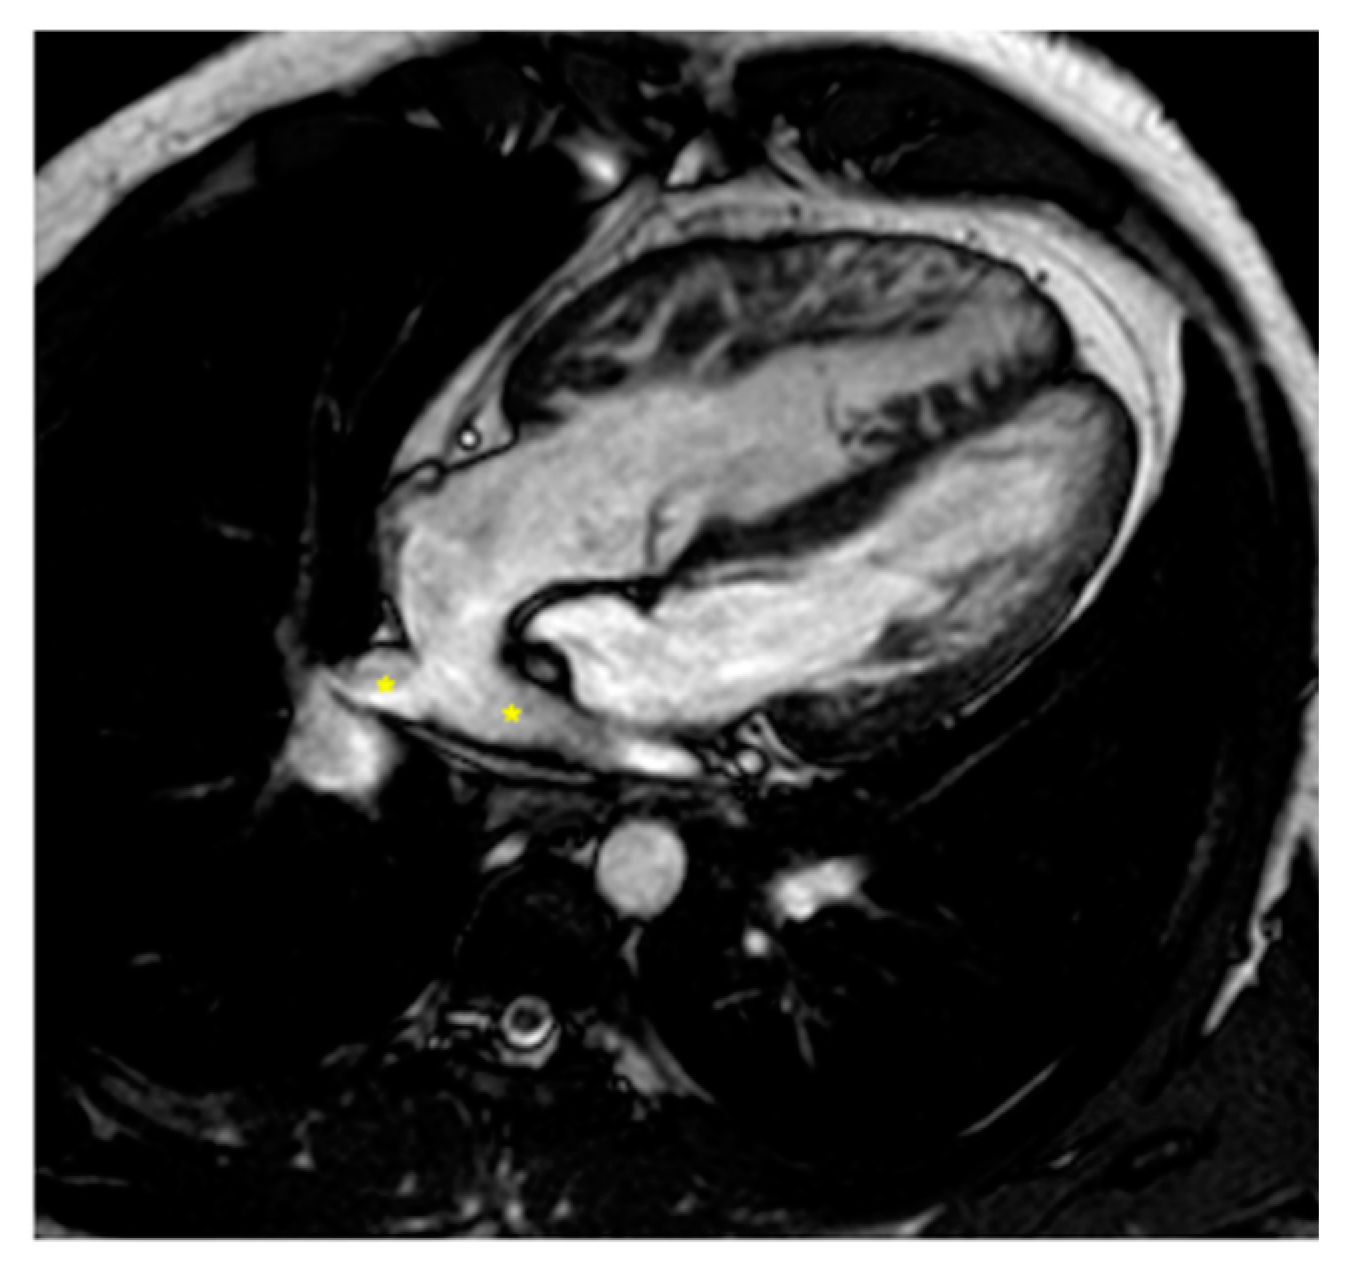

Complications after AtSO include baffle stenosis or leaks, systemic tricuspid valve (TV) regurgitation, and systemic right ventricle (sRV) dysfunction, with potential pulmonary hypertension often identified during routine imaging [44,45,46]. CMR is the gold standard for assessing sRV issues, offering detailed insights into heart morphology, function, and ejection fraction [12,40,47,48,49,50,51] thanks to the cine sequences, and it is especially recommended for evaluating systemic TV and baffles (Figure 2 and Figure 3) that are well studied from the 2D bSSFP, 3D whole heart, and angiographies [12,40]. Tricuspid regurgitation (TR) often stems from annulus dilatation, valve prolapse, or medial cuspid tethering, with occasional surgical damage to the valve leaflets [52,53,54]. CMR is also essential for detecting and assessing the severity of leaks and stenosis in the interatrial baffle [12,40,45] obtained through flow sequences. Myocardial performance, particularly fibrosis detection, is crucial, as it correlates with adverse outcomes—up to 60% of sRV patients exhibit LGE [45,55,56].

Figure 2.

Cine bSSFP image of D-TGA post-atrial switch operation using the Senning technique. The image shows the pulmonary veins (*) being redirected through the baffle into the right atrium and then to the subaortic positioned sRV.

Figure 3.

Cine bSSFP image of D-TGA following an atrial switch operation using the Senning technique. This image illustrates the pathway of the systemic veins, with the superior vena cava (*) and the inferior vena cava (§) shown.